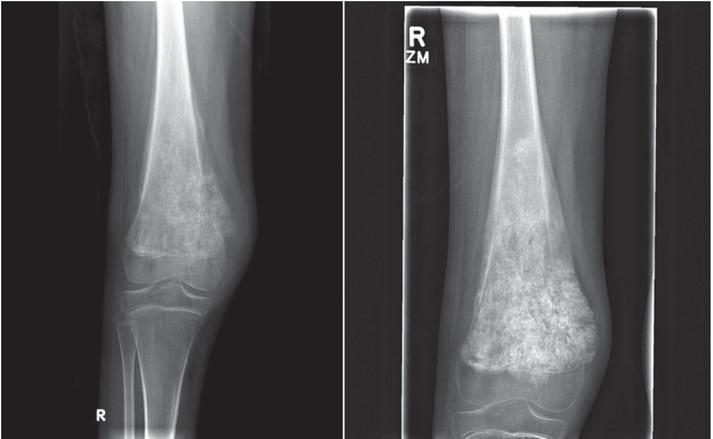

异位骨化:影像学与病理学综述

Heterotopic ossification: radiological and pathological review.

Background Heterotopic Ossification (HO) is a common condition referring to ectopic bone formation in soft tissues. It has two major etiologies, acquired (more common) and genetic. The acquired form is closely related to tissue trauma. The exact pathogenesis of this disease remains unclear; however, there is ongoing research in prophylactic and therapeutic treatments that is promising. Conclusions Due to HO potential to cause disability, it is so important to differentiate it from other causes in order to establish the best possible management.

摘要

背景 异位骨化(HO)是一种常见病症,指的是软组织中异位骨的形成。它有两种主要病因,后天性(更常见)和遗传性。后天性形式与组织创伤密切相关。该疾病的确切发病机制仍不清楚;然而,目前在预防性和治疗性治疗方面的研究很有前景。结论 由于HO有导致残疾的可能性,为了制定最佳治疗方案,将其与其他病因区分开来非常重要。